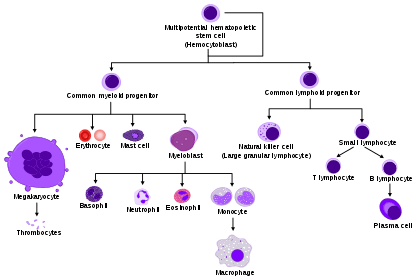

Hematopoietic stem cells (HSCs) or hemocytoblasts are the stem cells that give rise to all the other blood cells through the process of haematopoiesis.[1] They are derived from mesoderm and located in the red bone marrow, which is contained in the core of most bones.

HSCs give rise to both the myeloid and lymphoid lineages of blood cells. (Myeloid cells include monocytes, macrophages, neutrophils, basophils, eosinophils, erythrocytes, dendritic cells, and megakaryocytes or platelets. Lymphoid cells include T cells, B cells, and natural killer cells.) The definition of hematopoietic stem cells has evolved since HSCs were first discovered in 1961.[2] The hematopoietic tissue contains cells with long-term and short-term regeneration capacities and committed multipotent, oligopotent, and unipotent progenitors. HSCs constitute 1:10.000 of cells in myeloid tissue.